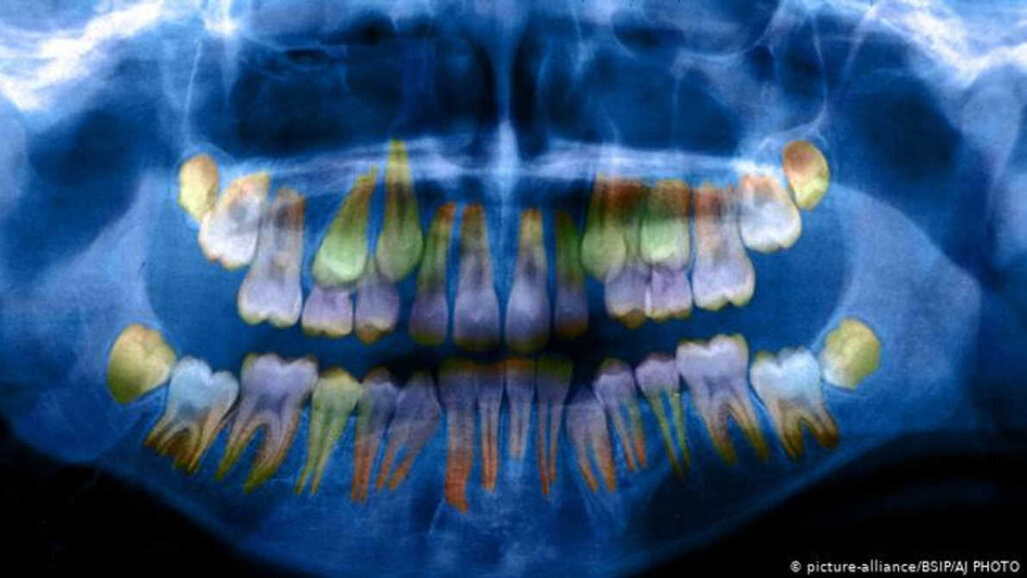

Najważniejszym odkryciem było to, że w zębach dzieci można zaobserwować, czy były one narażone na czynniki stresowe we wczesnym wieku. Wg dr. W. Thomasa Boyce'a, prof. pediatrii i psychiatrii dziecięcej na Uniwersytecie Kalifornijskim w San Francisco przedstawił na spotkaniu AAAS poszczególne warstwy, które tworzą szkliwo zębów, są cieńsze i mniej gęste w przypadku narażenia na stres, co „zwiększa podatność na uszkodzenia zębów”. Zmiany te można zmierzyć, badając stan pierwotny zębów w modelu 3D w oparciu o radiogram.